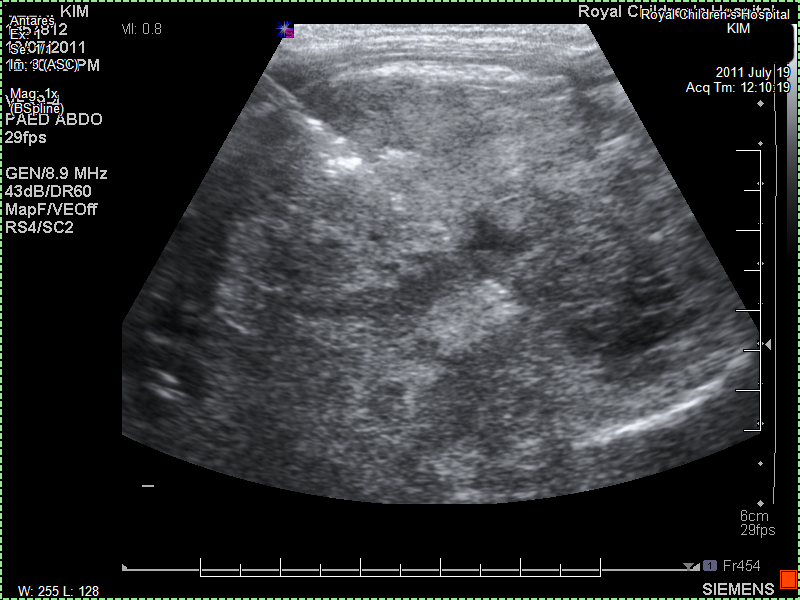

The paediatrician feels with her hands something in Kim's tummy. She gives us a gentle warning that there may be something there and refers us to a local imaging laboratory. She phones and makes sure we can be seen that same day. In the laboratory they ask us to wait. They tell us that there is an undefined mass near her left kidney. They don't want to say more. Ultrasounds are not that precise and we should go immediately back to the paediatrician. The paediatrician sees us almost immediately and tells us that it is not yet clear what Kim has but that it could be serious. At the same time she tries to comfort us with the knowledge that these days there are many new treatments. She doesn't want to use the word cancer but it is almost implied. She tells us she will refer us to the hospital to find out what it is exactly. The Monash is closer to us, but seen our previous experiences we ask to be referred to the Royal Children's Hospital. We insist that we have no trust in the Monash and will go to the Royal Children's. Which is traffic wise just a little further. The paediatrician mentions the close cooperation and that care should be the same. We are not convinced and the paediatrician is recognizes our resolve and understands why. She refers us to the Royal Children's Hospital emergency department with suspected cancer.

I have arranged an ultrasound scan of Kim's abdomen which shows a left sided mass, thought to be arising from her left kidney."